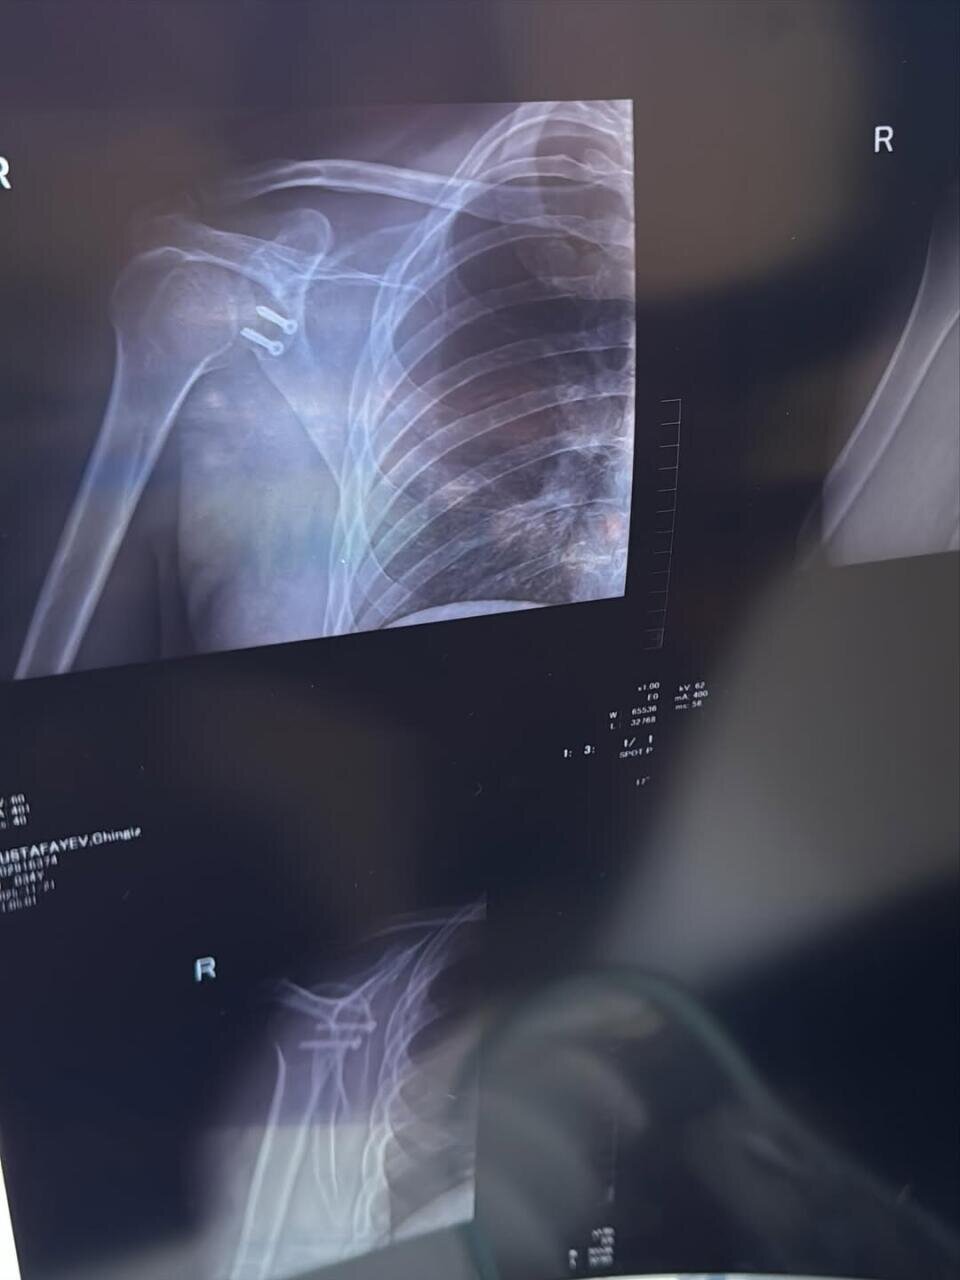

Müğənni Çingiz Mustafayev əməliyyat olunub.

Müğənni çiynində olan problemə görə bıçaq altına yatdığını açıqlayıb.

"15 il ərzində çiynim 7 dəfə çıxıb. Hər dəfə eyni ağrı, qorxu, narahatlıq... İdman da, aktiv həyat da tam mümkün olmurdu. Hər dəfə özümə deyirdim: hələ tezdir, bir az da gözləyim bir söznən iş güc və sairə... Amma 2 ay əvvəl sonuncu dəfə çiynim çıxanda anladım ki, artıq bu məsələni həll etməyin vaxtı gəlib. Dünən əməliyyat olundum. İndi uzun bir reabilitasiya dövrü başlayır. Əməliyyat önəmlidir, amma ən çətini sonraki mərhələdir: səbir, intizam və özünü qorumaq", - o qeyd edib.